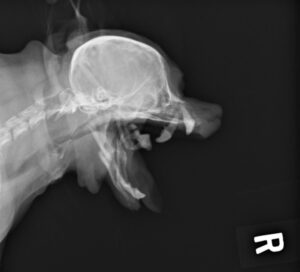

重度の歯周病で両側の下顎の病的骨折をしているワンちゃんが来院されました。悪い歯の抜歯と下顎のプレート固定(TITAN LOCK1.2mm使用)で対応しました。退院後しっかりご飯が食べられるようになりました。よかったね。